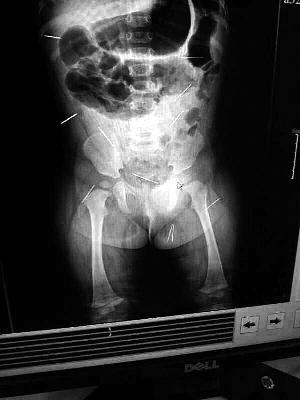

“要不是當(dāng)初那幾個紅點,可能到現(xiàn)在我們還不知道孩子身體里有鋼針!”昨天,在兒童醫(yī)院住院處,萱萱爸爸范先生稱,日前原本很愛笑的萱萱突然變得有些焦躁,一抱起來就哭,孩子母親偶然間在萱萱屁股上發(fā)現(xiàn)了幾個小紅點兒,原以為是蚊蟲叮咬,就醫(yī)結(jié)果卻讓人不寒而栗。“醫(yī)院拍出的片子上,萱萱的體內(nèi)有12根鋼針,插滿臀部、腹腔、骨盆等各個部位。”范先生介紹,因為鋼針已深入體內(nèi),要是孩子不哭鬧,他們很難發(fā)現(xiàn)。

北京晨報記者了解到,目前體內(nèi)的12根鋼針多分布在孩子的臀部,一根在腹部,其余3根在胸腔附近,其中一根很接近心臟(如圖)。“因為孩子太小,醫(yī)生們害怕取針的時候?qū)λ斐蓚Γ谛厍桓浇?針可能會威脅她的生命”。